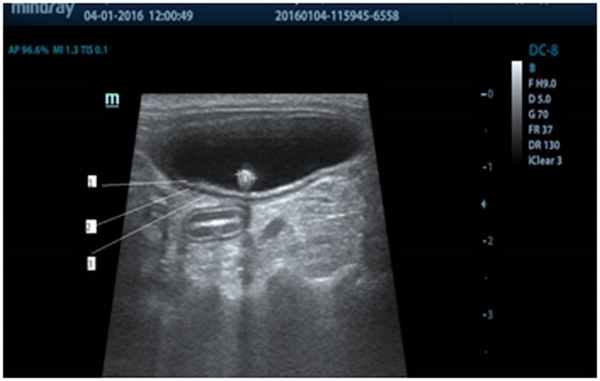

Рис. 1 - УЗ изображение мочевого пузыря в норме

С точки зрения УЗ-диагностики мочевой пузырь – это полый орган, ан эхогенный по структуре с гипоэхогенной стенкой расположенный в каудовентральной области брюшной полости. (рис.1) В норме все слои хорошо дифференцируются: слизистый и серозный слои гипоэхогенны (рис.3 – 1,3), мышечный слой практически анэхогенен (рис.3-2).

При умеренном наполнении мочой, один из самых легко обнаруживаемых органов. Во время исследования животное укладывается в дорсальной или латеральной позиции. Сканирование проводится трансабдоминально. Если животное агрессивное или лишний стресс опасен и угрожает жизни животного, допускается визуализация мочевого пузыря в положении стоя. Плоскости сканирования мочевого пузыря – сегментарная и сагиттальная.

Для полной визуализации органа, необходимо выполнение двух условий – умеренное наполнение мочевого пузыря и опорожненная прямая кишка. (рис. 1) Второе условие необходимо, дабы исключить деформацию мочевого пузыря кишкой, заполненной каловыми массами, что ошибочно можно принять за конкремент или опухоль (рис.2 -прямая кишка смещает дорсальную стенку мочевого пузыря). При опорожненном мочевом пузыре возможна катетеризация и введения стерильного изотонического 0,9% раствора натрия хлорида в мочевой пузырь или внутривенная инъекция фуросемида из расчета 2 мг на кг веса животного.